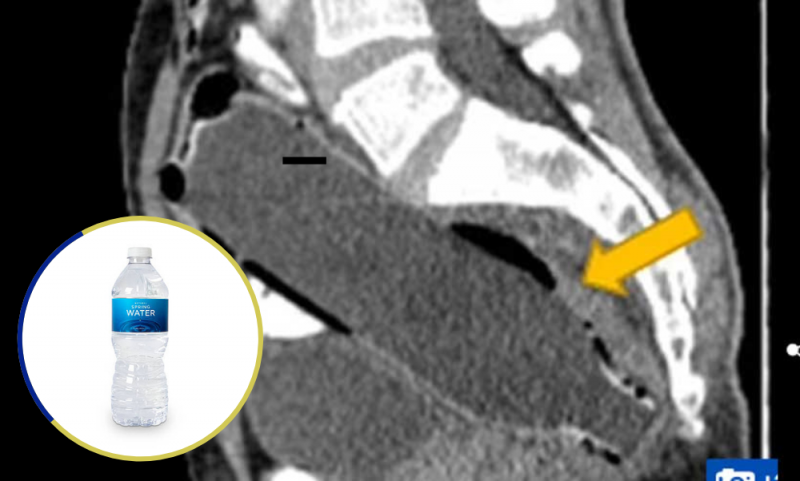

Creyó que estaba estreñido pero doctores le encontraron una botella de agua en el intestino grueso

Los hechos ocurrieron en Sarí, la capital de la provincia de Mazandarán, ubicada en el norte de Irán, donde el sujeto de 50 años, cuya identidad no fue revelada, tampoco confesó a los médicos del Hospital Imam Khomeini lo que estaba ocurriendo hasta que un “CT scan” (tomografía computadorizada) dejó al descubierto su secreto.

La botella medía 7 pulgadas y media.

Según un artículo del Clinical Case Reports Journal, el individuo empujó el fondo de la botella pensando que de esta forma podía sacarla más fácilmente agarrando la parte superior; no obstante, no tuvo éxito y el objeto quedó atorado en el intestino grueso.